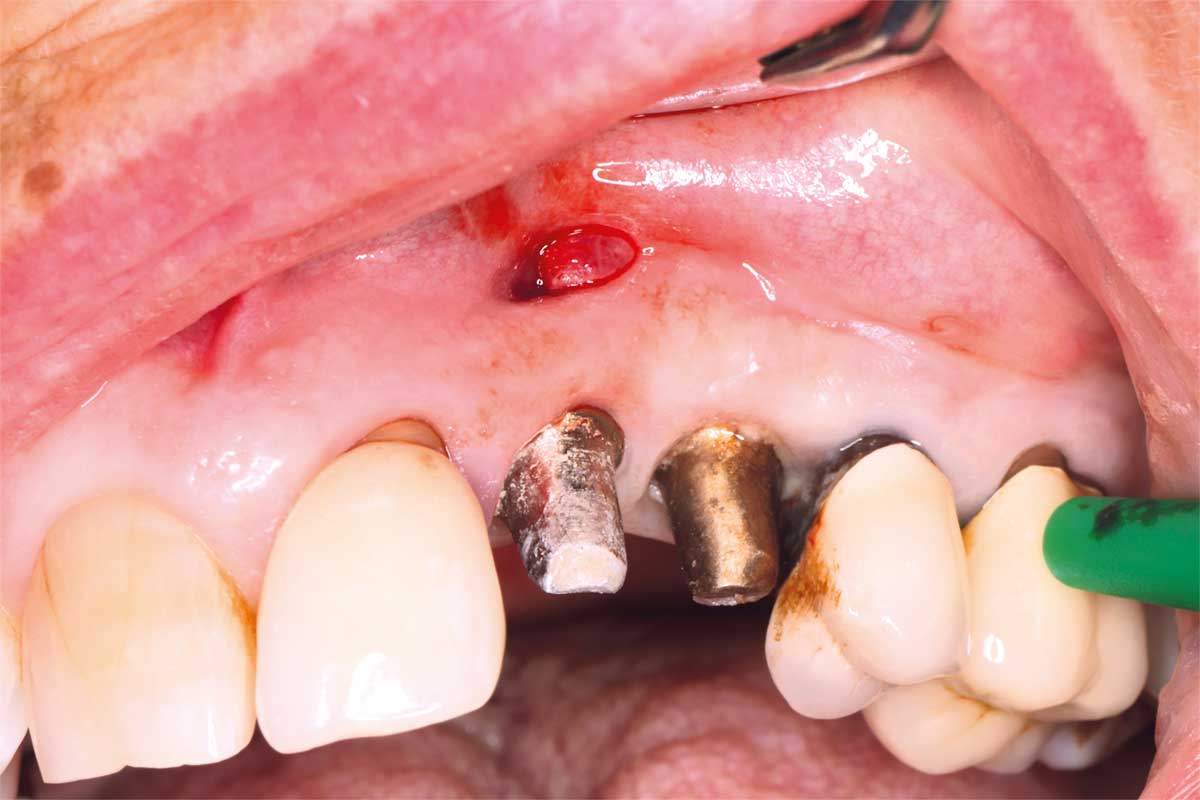

Ridge management following implant explantation - Dr. P.-Y. Gegout & Prof. Dr. O. Huck

Pre-operative: loss of interdental papilla between 12 and 11 associated with gingival inflammation and pus